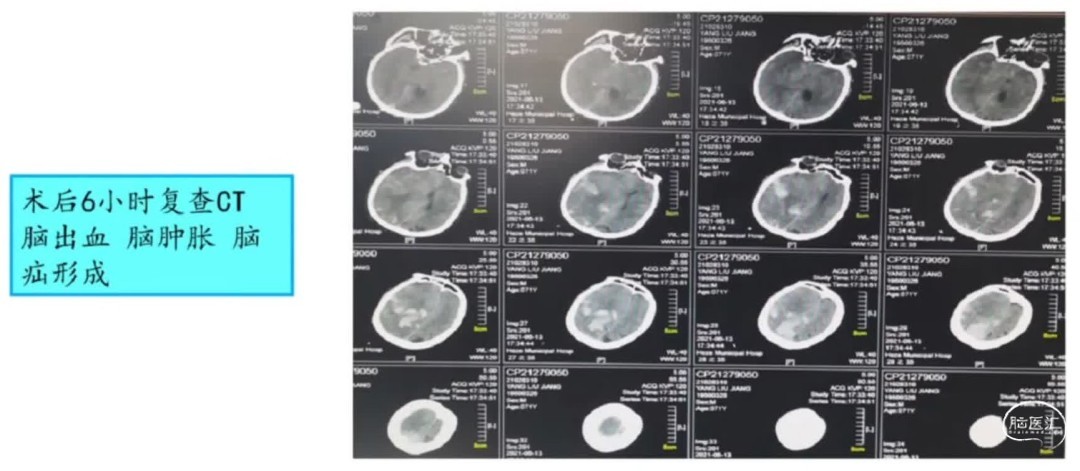

2、远端血管闭塞多是检塞事件,栓子随时可能发生动态变化,术前NIHSS评分高,可能是大血管闭塞且侧枝代偿差,已经形成较大的核心梗死,因栓子远端移位术中表现为远端血管闭塞,此时尽管开通满意,但术后过度灌注损伤、脑出血风险比较高,临床预后并不满意,此时应适可而止。